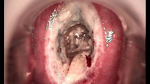

• 宮頸息肉宮頸息肉

• 宮頸息肉 leep術后宮頸息肉 leep術后

• 宮頸息肉 leep術一周后宮頸息肉 leep術一周后

• 宮頸息肉 leep術兩周后宮頸息肉 leep術兩周后

• 宮頸息肉 leep術三周后宮頸息肉 leep術三周后

• 宮頸息肉 leep術50天后宮頸息肉 leep術50天后